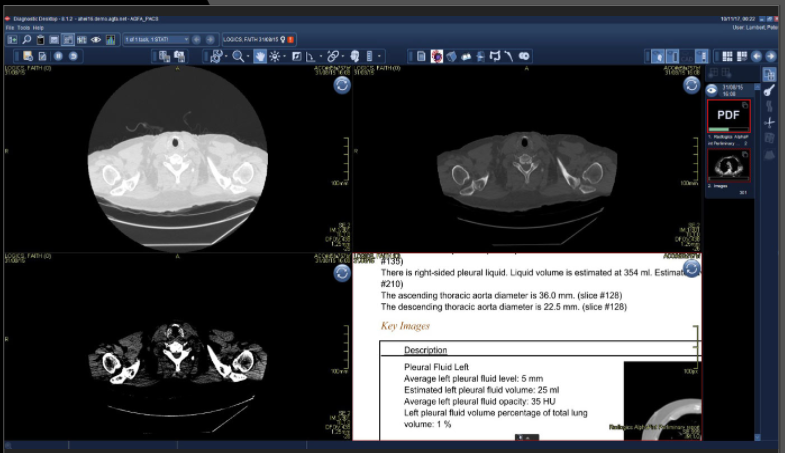

Решение Virtual Resident от RADLogic ищет, измеряет, характеризует и готовит предварительный отчет о результатах, используя анализ изображений машинного обучения для обработки огромного количества данных изображений, связанных с КТ, МРТ и рентгеновскими лучами. В течение нескольких минут черновик отчета, включающий основные изображения, доставляется в систему отчетов радиолога, что позволяет радиологам сосредоточить свое время и внимание на диагностике.

Выводы виртуального резидента объединяются с данными медицинской карты пациента. Каждая часть информации видна для просмотра и подготовки окончательного диагностического отчета, включая идентификацию пациента, метод визуализации, результаты (включая количественные измерения) и ключевые изображения. Платформа использует автоматический анализ изображений и, следовательно, не зависит от человека, что сводит к минимуму вероятность несоответствий.

Программное обеспечение RADLogics на базе искусственного интеллекта включает в себя алгоритмы, которые не только обнаруживают аномалии на компьютерной томографии грудной клетки и рентгеновских снимках, но также предоставляют радиологу автоматические предупреждения о сортировке, чтобы гарантировать своевременное рассмотрение потенциальных результатов. Решения компании обеспечивают количественный анализ компьютерной томографии и рентгеновских снимков для пациентов с подозрением на заболевание, включая процентную оценку объема, которая может помочь отслеживать результаты с течением времени. Доступ к этим приложениям поможет удовлетворить растущий спрос на эти решения, способные обрабатывать 1 миллион КТ и 10 миллионов рентгеновских исследований в день через облачную платформу RADLogics. Приведенные цифры наглядно демонстрируют, что анализ изображений ИИ позволяет сделать интерпретацию рентгенологических изображений более быстрой и эффективной.